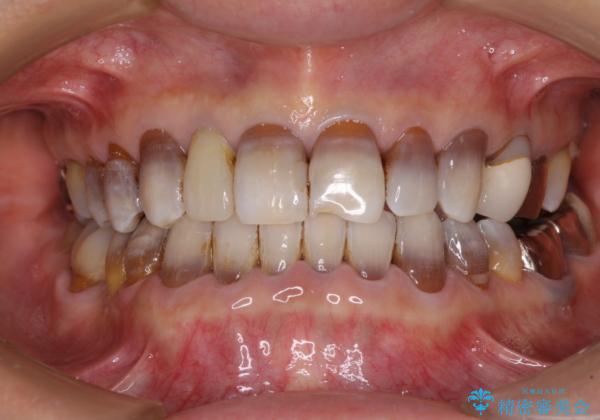

下の歯が前に出てしまう咬み合わせを治したい インビザラインによる矯正治療

- 前歯のクロスバイトを気にして来院された患者様です。

骨格的に下顎が前方位ではありますが、歯並びが改善されれば正常咬合となることが分かったため、インビザラインを用いて咬み合わせを改善していくこととしました。